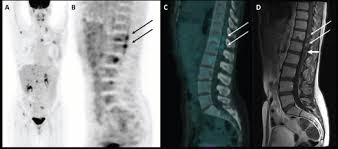

Breast Cancer A Ct Scan After Breast Conserving Surgery Before Download Scientific Diagram from www.researchgate.net Ct scans and cat scans describe the same imaging test. This test may reveal whether breast cancer has spread to the bone. Where can people get more information about ct? Definition purpose description preparation aftercare risks normal results. Detection of cancer prior to onset of symptoms (via several tests/imaging). It can also show changes caused by other medical conditions. A radiographer operates the scanner. Bone scans, positron emission tomography (pet), and computed tomography (ct) all continue to be employed alone or in combination for the detection of breast cancers suspected to have spread.